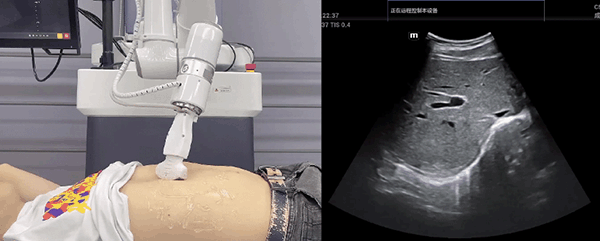

艾利特機器人末端搭載超聲探頭,可以對淺表小器官和外周血管、腹部(肝、膽、胰、腎等器官)進行超聲檢查。

目前,艾利特機器人在生物醫藥、醫療健康領域的賦能已有顯著進展,艾利特協作機器人應用場景覆蓋了臨床試驗、試管檢測、拭子采集、試管搬運、熒光檢測、康復治療、超聲掃查、導診、消毒、微創治療、針灸刮痧等。